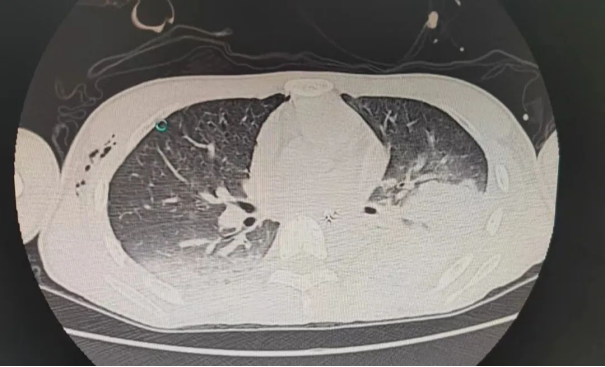

“先抢救,送往ICU!” 上午6时,患者被送往ICU,当时患者血压低、心率快、呼吸窘迫、血氧下降、右侧胸壁皮下气肿且进行性增大,气道持续引出大量鲜血,结合影像学和检验结果,诊断为肺挫伤、创伤性湿肺、右侧血气胸、左侧肋骨骨折、创伤性休克、创伤性凝血障碍、蛛网膜下出血、颅骨骨折。

ICU曾振宏医生、王志敏医生和廖琴住院总医师立即争分夺秒地实施救治,行气管插管呼吸机通气、胸腔闭式引流、开通深静脉通道补液扩容、血管活性药物升压、止血、输血等处理,同时再次行床边超声排查有无其他部位迟发性出血。ICU张春云主任以最快时间赶到现场指导抢救,为患者行气管镜检查,发现出血“元凶”为左侧背段支气管,经积极药物止血和气管镜下止血效果不佳,气道内仍在大量出血,如果不及时止血,患者缺氧和休克无法改善,生命将危在旦夕。

虽然度过了最凶险的时刻,但后续的治疗仍不能掉以轻心。患者为创伤性湿肺合并血气胸,呼吸机参数必须灵活调整,既保证氧合,又不产生气压伤;时刻关注生命体征和各个器官功能,做好神经系统和各个脏器功能的维护;液体管理上,休克被纠正后需实现负平衡,让肺保持“干一些”的状态;此外患者还存在肺泡弥漫性出血,为保证气道通畅,每天需要行多次气管镜清除积血……ICU医护人员通过一系列精细化的管理措施,为患者尽快康复保驾护航。